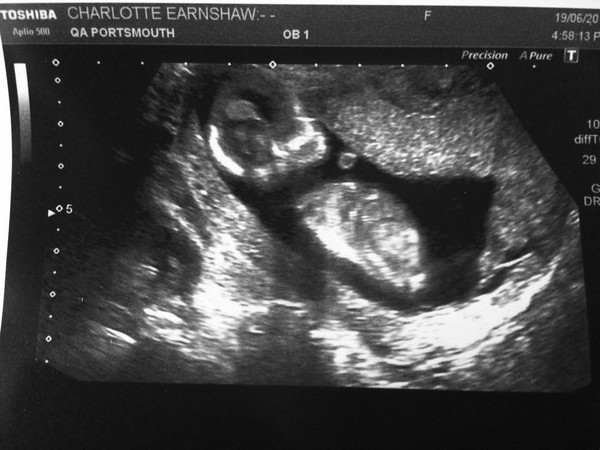

Scan went really well. Baby was fast asleep at first and really annoiyed to be woken up! Here is baby sucking their thumb. Hope what a lovely cutey baby you have!

Great scan pic Hope - it's amazing how much they develop in such a short space of time.